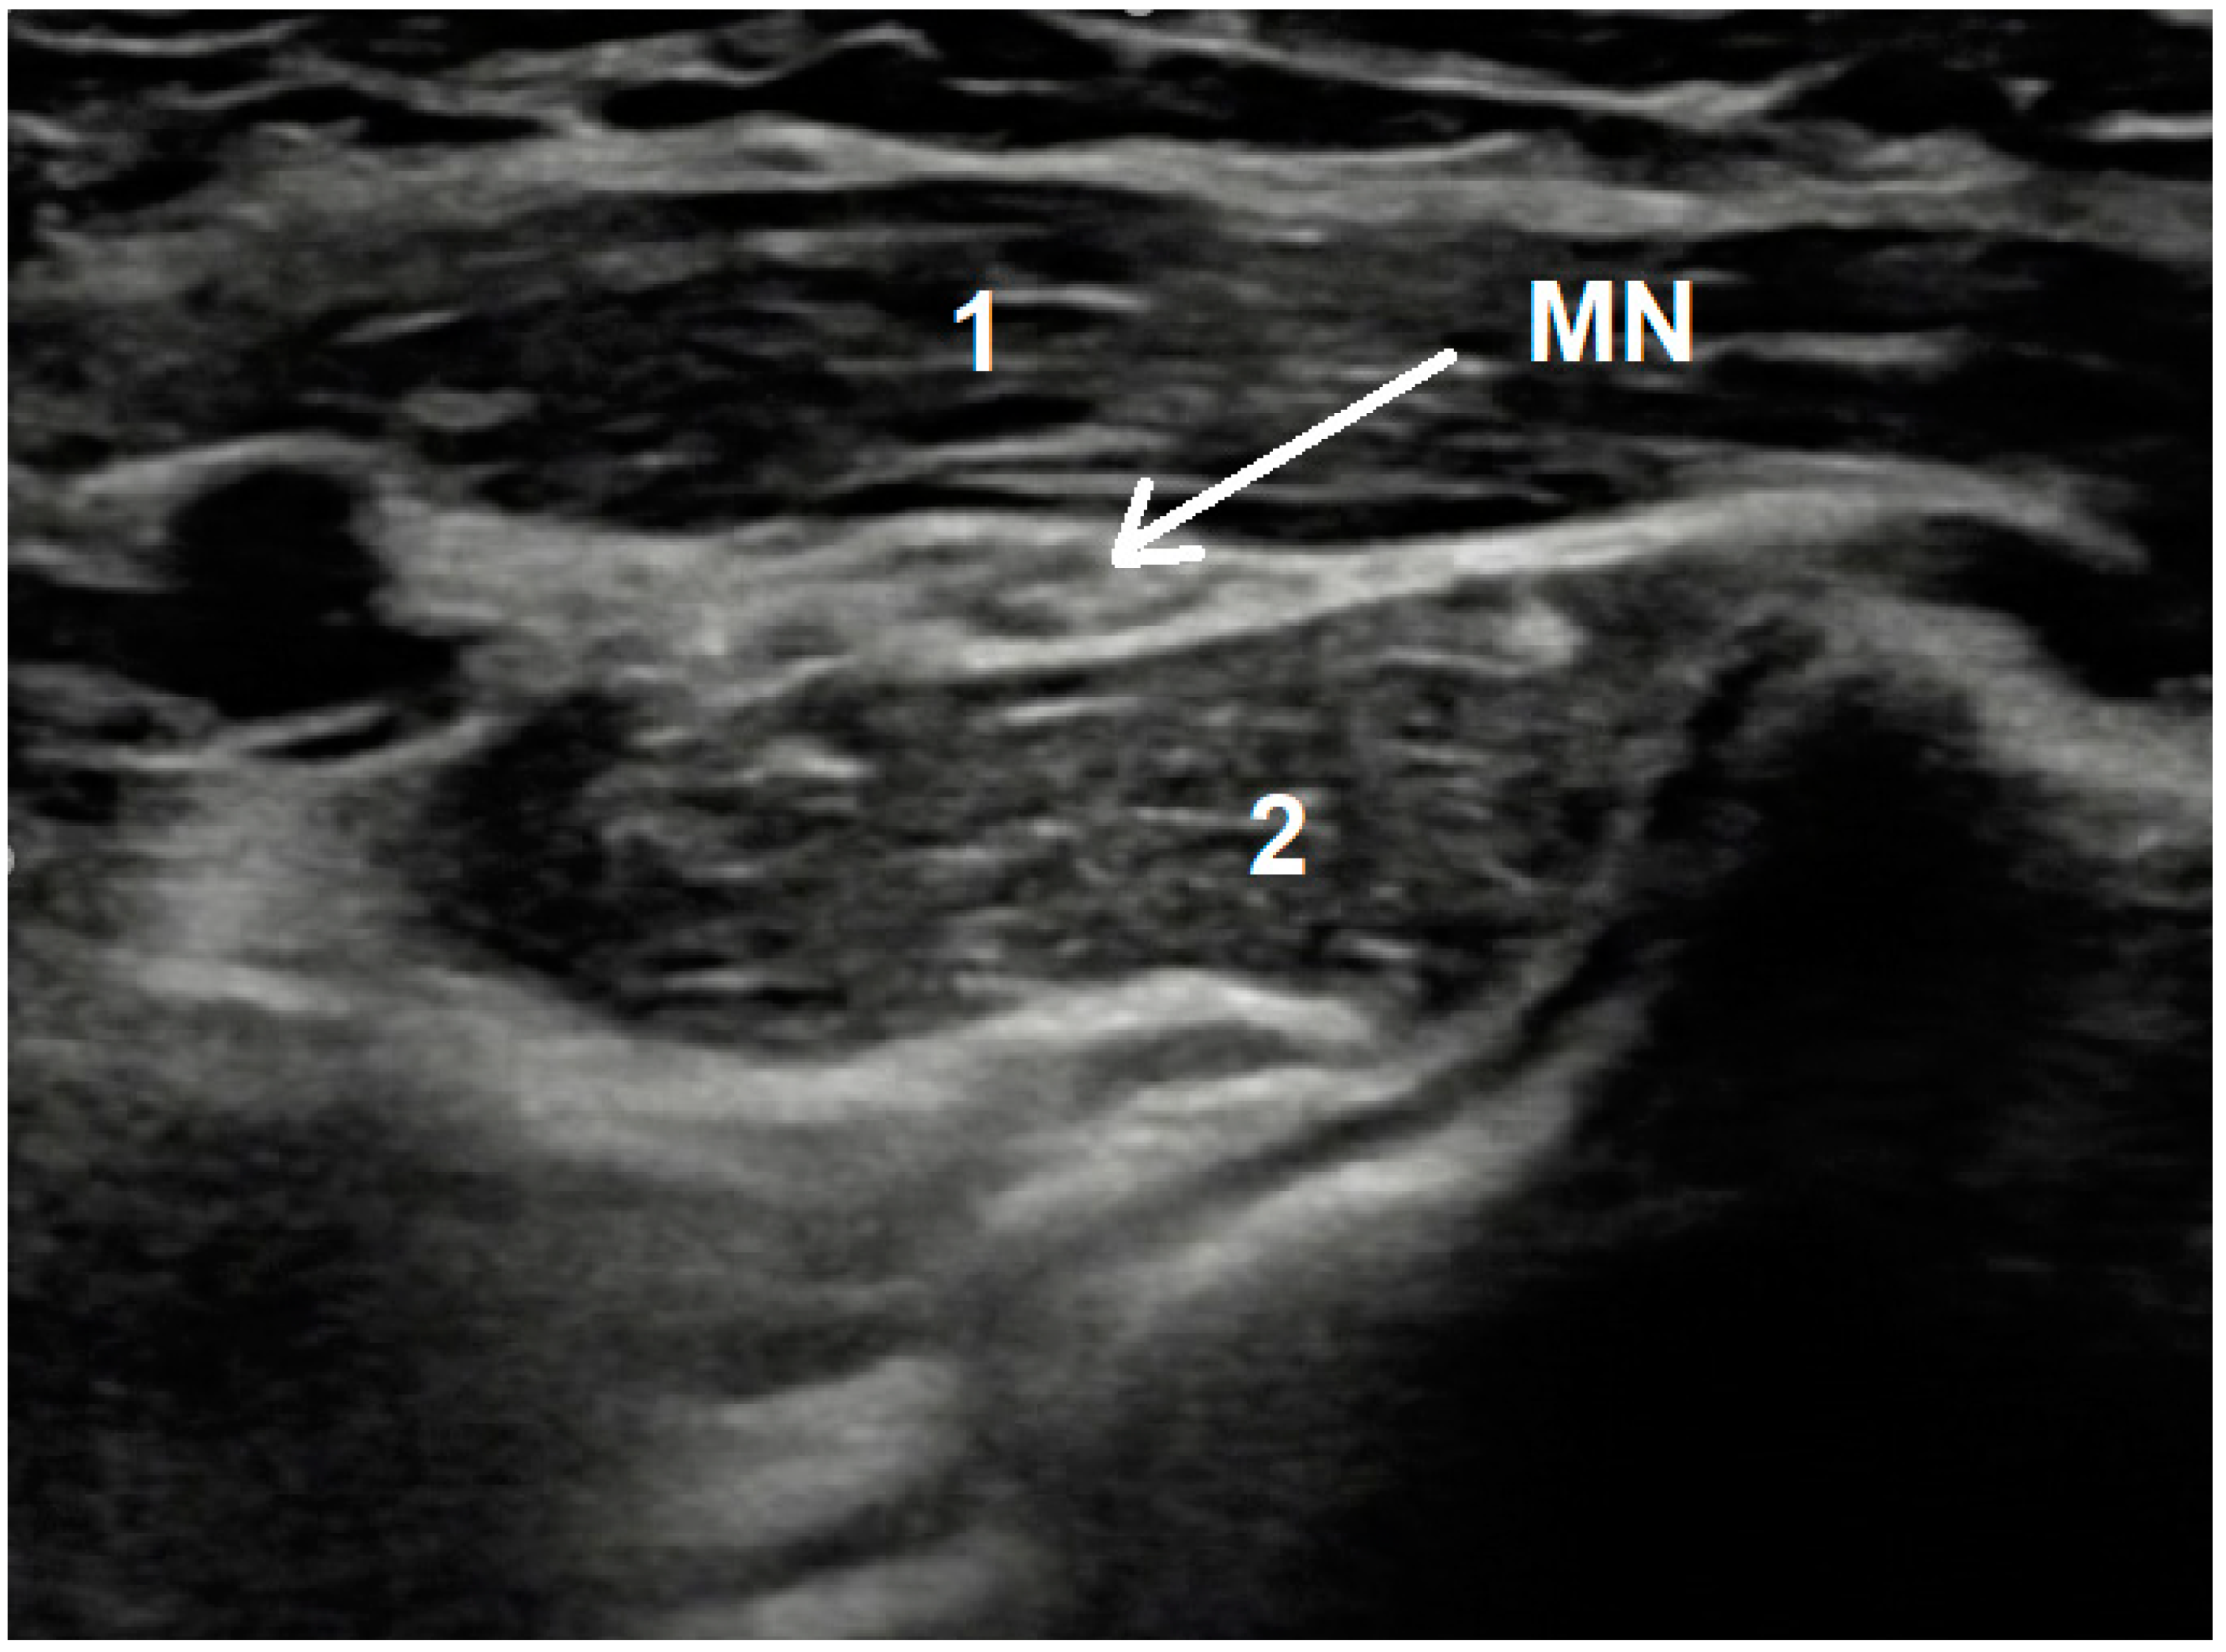

In contrast to CTS, both magnetic resonance and ultrasonographic imaging are not recommended in a PS workup because of the lack of current clinical evidence [12]. However, USG examination sometimes can visualize the MN compression site between PT heads—Figure 2.

Figure 2.

Exemplary image seen during USG examination of pronator syndrome showing medial nerve compression. MN—Medial Nerve; 1—humeral head of Pronator Teres muscle; 2—ulnar head of Pronator Teres muscle; longitudinal cross section Mov. 1 Forearm USG examination result showing median nerve thickening distally to compression site.